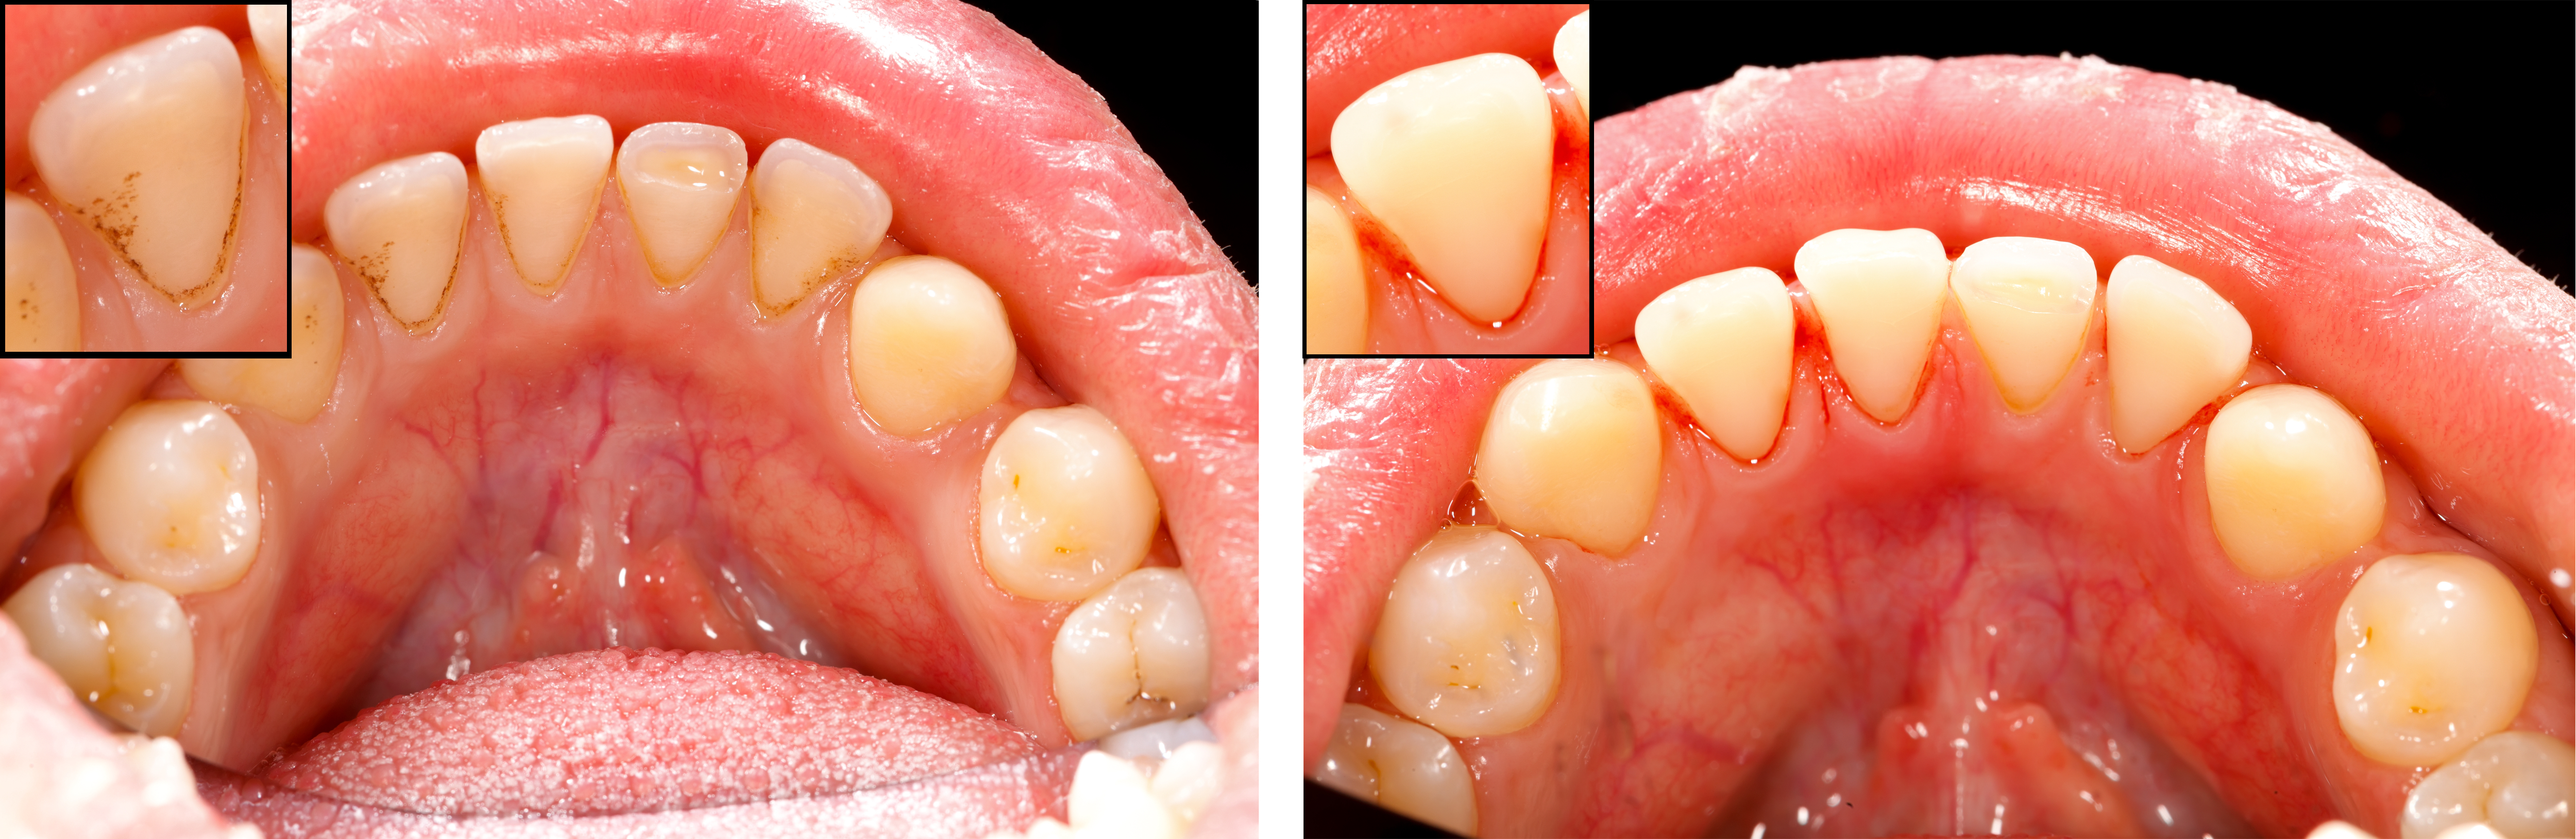

スケーリング前,後写真

炎症がなくなってきたらむくでいた歯茎はどんどんなくなるでしょうね?

相対的には歯は長いように見え、歯と歯の間は大きく見えます。

また、スケーリング後、しびれる症状も現れますが…

歯根の表面(セメント質, cementum)を囲んでいた、歯石がとられた後はセメント質が現れます。

セメント質はエナメルとは違い、歯の中(pulp)にある神経がしびれることを感じられる構造になっています。